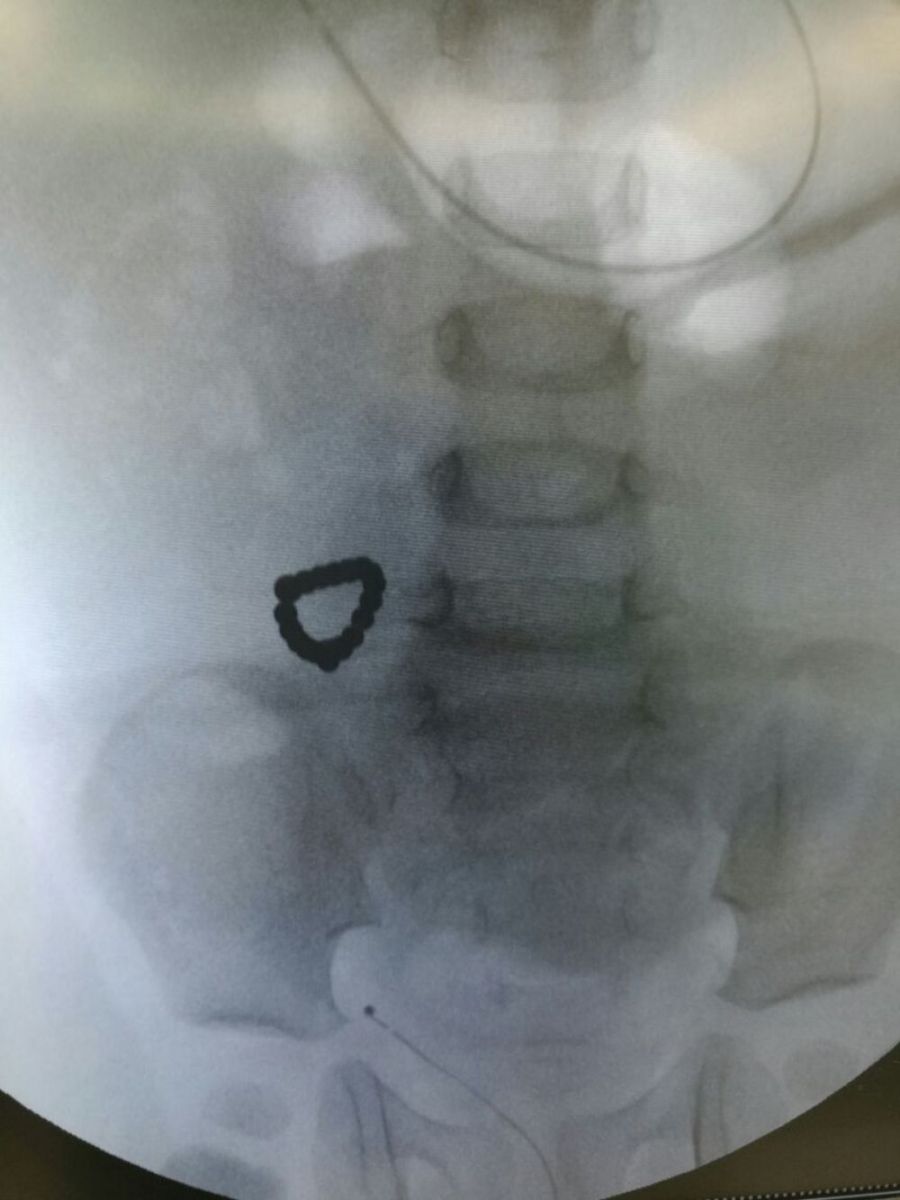

Aýrýhanaǵa kelmes buryn balanyń asqazany qatty aýyryp, ishi ótken. Balany rentgennen ótkizgennen keıin, rentgen sýretinen balanyń asqazanynda dóńgelek moıynǵa taǵatyn alqa baryn bilgen. Aǵzadan áshekeıdi qoldan shyǵara almaǵannan keıin operasıa jasaýdy bastaıdy.

Operasıany jasaý barysynda onyń magnıt ekenin bilgen dárigerler, dereý qaýiptiń aldyn alyp, tez sheshim qabyldaı bildi.